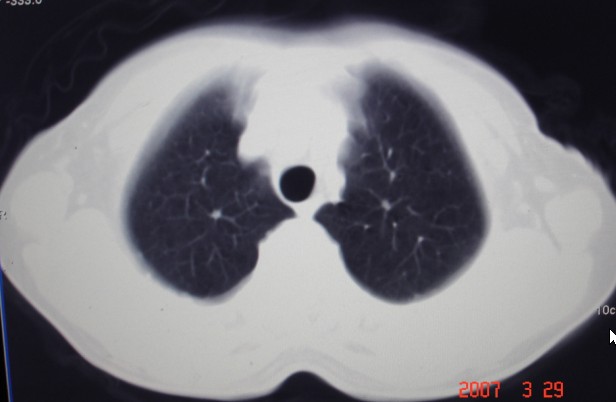

女,60岁咳嗽咳痰7天,痰中带血,有发热史,血象大约6000

双肺多发病灶,呈多形性,多叶分布,左上叶尖后段靠胸壁病灶伴有空洞,边缘模糊,与胸壁呈刀切征.

考虑混合感染以tb为主.

多灶,多形,少聚,少块。卫星灶,空洞影,树芽征,结核可能性大